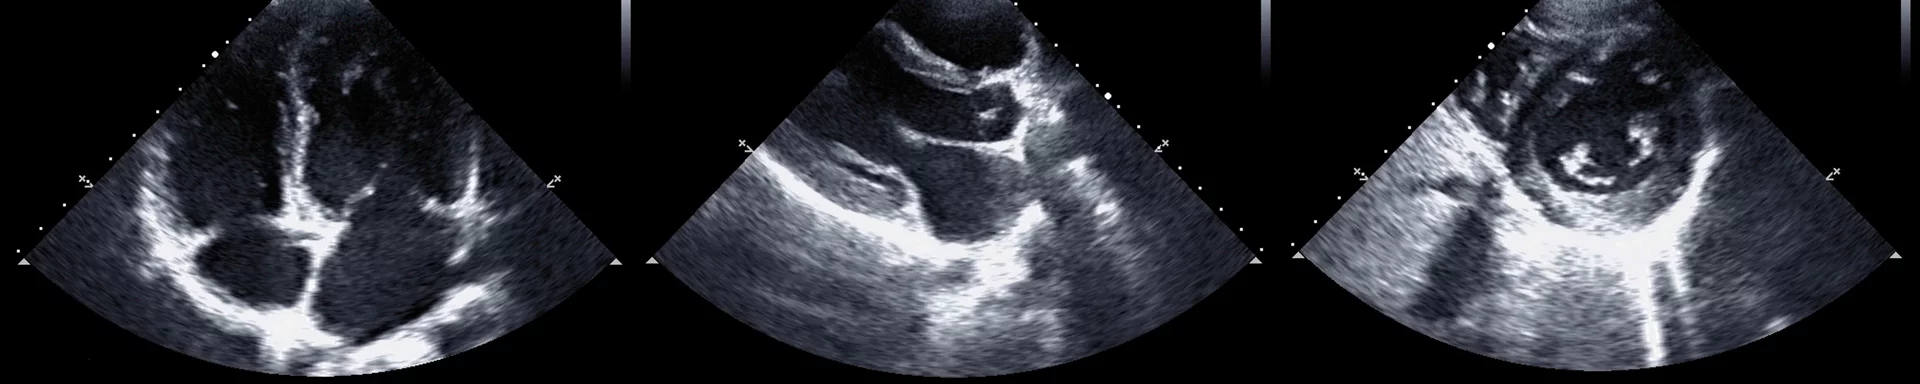

Anatomie und Schnittebenen

LV-Funktionsanalyse

Fokus Aortenklappe

Fokus Mitralklappe

Rechtsherzechokardiographie